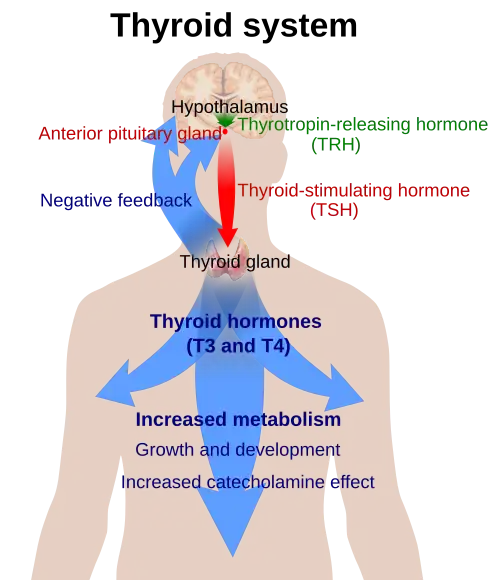

Secretion of the two thyroid hormones is regulated by thyroid-stimulating hormone (TSH), which is secreted from the anterior pituitary gland. TSH is regulated by thyrotropin-releasing hormone (TRH), which is produced by the hypothalamus.[2]

Regulation

The production of thyroxine and triiodothyronine is primarily regulated by thyroid-stimulating hormone (TSH), released by the anterior pituitary gland. TSH release in turn is stimulated by thyrotropin releasing hormone (TRH), released in a pulsatile manner from the hypothalamus.[39] The thyroid hormones provide negative feedback to the thyrotropes TSH and TRH: when the thyroid hormones are high, TSH production is suppressed. This negative feedback also occurs when levels of TSH are high, causing TRH production to be suppressed.[40]

TRH is secreted at an increased rate in situations such as cold exposure in order to stimulate thermogenesis.[41] In addition to being suppressed by the presence of thyroid hormones, TSH production is blunted by dopamine, somatostatin, and glucocorticoids.[42]